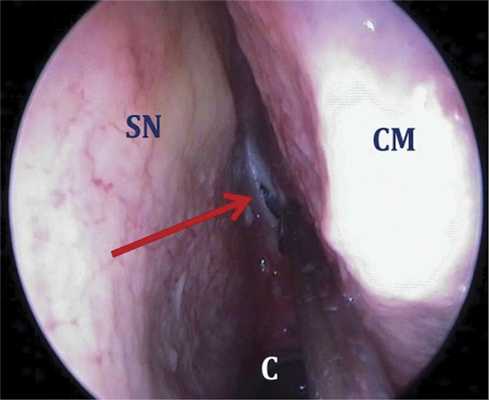

Наиболее простым и относительно безопасным является парасептальный доступ — именно с него рекомендуется начинать освоение хирургических вмешательств на клиновидной пазухе. Для этого необходимо ввести эндоскоп в верхний носовой ход и затем аккуратно сместить элеватором среднюю и верхнюю носовые раковины в целях визуализации естественного соустья клиновидной пазухи (рис. 4). Рис. 4. Левая половина полости носа, анатомический препарат, эндоскоп 0º. Парасептальный доступ к клиновидной пазухе начинают с латеропозиции средней носовой раковины (сoncha nasalis media — CM). Соустье клиновидной пазухи (отмечено красной стрелкой) находится на 10—15 мм выше костного края хоаны (сhoana — С). SN — перегородка носа (septum nasi). The paraseptal approach to the sphenoidal sinus begins from the lateral positioning of the middle turbinated bone (concha nasalis media, CM). Anastomosis of the sphenoidal sinus (indicated by the red arrow) is localized 10—15 mm above the bony edge of the choana (choana, С). The nasal septum (septum nasi, SN). При измененных анатомических соотношениях либо патологическом процессе в сфеноэтмоидальном кармане визуальная идентификация соустья может быть затруднительной. В такой ситуации соустье клиновидной пазухи, которое обычно располагается на 10—15 мм выше верхнего края хоаны, между перегородкой носа и верхней носовой раковиной на границе ее нижней и средней третей, определяется путем пальпации пуговчатым зондом или кюреткой.